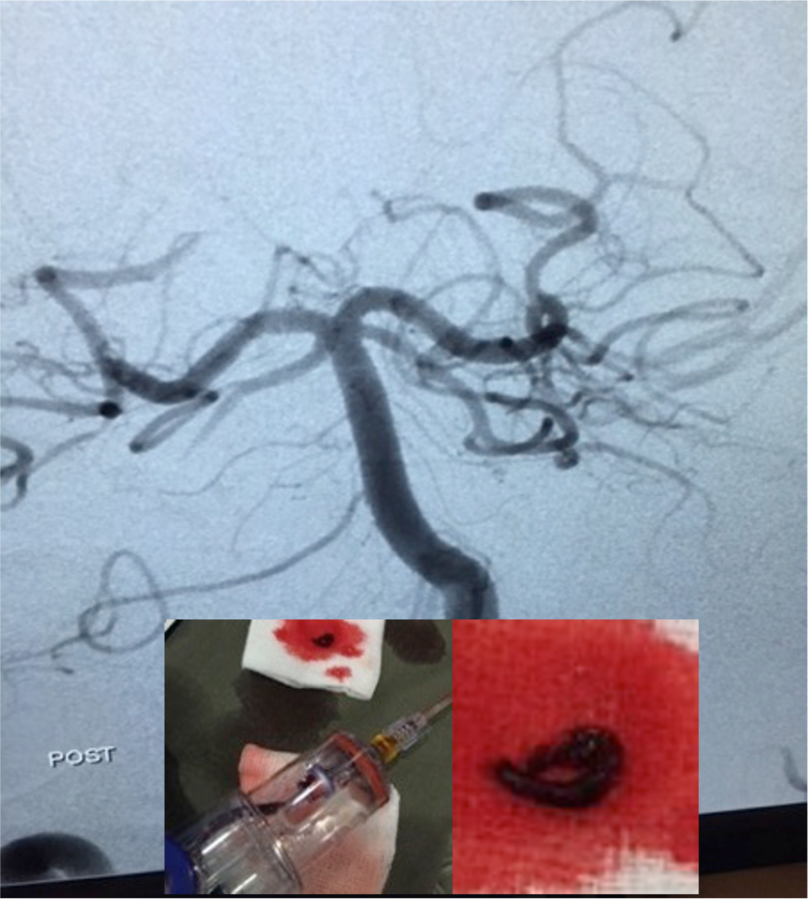

The Control Mechanical Thrombectomy System has been used in thousands of procedures to remove blood clots from the peripheral, coronary, and neuro vasculature.

Coronary thrombectomy in the heart treats acute myocardial infarction (AMI); neurovascular thrombectomy in the brain treats acute ischemic stroke; and peripheral thrombectomy treats peripheral arterial disease (PAD), chronic total occlusion (CTO), deep vein thrombosis (DVT), pulmonary embolism (PE), hemodialysis access occlusions, and other conditions. Certain technologies and procedures remove more healthy blood than others creating a patient safety risk.

"Targeting, control, and reducing blood-loss is important when removing blood clots," said Lawrence S. Kronick, co-Founder Control Medical Technology. "Control's system includes peripheral and coronary thrombectomy catheters powered by a single-use mechanical aspirator or electric pump for improved precision and force with low-blood-loss. We are excited to partner with Shanghai Easy-Flow to commercialize the Control platform in China."

Control's platform includes the FDA cleared Control 5 -11F Mechanical Thrombectomy System indicated for peripheral vasculature, the Control RX-LP Mechanical Thrombectomy System indicated for peripheral and coronary vasculature, and the Control Mechanical Aspirator indicated for peripheral or coronary vasculature plus use as a high-performance 250ml piston-syringe. The Control's electric pump-based PULSE & PULSE Retriever Basket is under development and not for sale at this time. Control Medical Technology's platform is protected by issued and pending patents www.AspirationMedical.com.